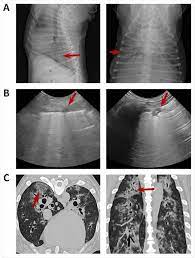

Surprising Lung Cancer Symptoms from img.webmd.com These signs are not specific for bronchitis and can also be seen with many other diseases including heart failure, pneumonia, allergic lung disease and lung cancer. Antibiotics may be prescribed to treat pneumonia. Adenocarcinoma of the lung in dogs. Sometimes, people with pneumonia may have symptoms similar to lung cancer. However, primary lung cancers are being seen more frequently over the last 20 years. However, some dogs only experience weight loss (despite a good appetite) and/or lack of energy. In addition it is quite unlikely that the radiologist would mistake lung cancer for pneumonia. Unlike some other types of cancer, there are some concerning symptoms that arise in the earlier stages of primary lung cancer for dogs that should immediately alert you that something is wrong.

Symptoms of primary and metastatic lung cancer are similar, although dogs with metastatic disease don't cough as much, according to the merck veterinary manual. Fungal pneumonia, also called mycotic pneumonia, refers to a fungal infection of the lungs that results in pneumonia caused by breathing in one of many different fungi spores. This time we will discuss lung cancer in dogs symptoms, their life expectancy, diagnosis using x ray, cancer treatment, and stages of lung cancer in dogs. However, some dogs only experience weight loss (despite a good appetite) and/or lack of energy. Other symptoms include exercise intolerance, lethargy and weight loss. These signs are not specific for bronchitis and can also be seen with many other diseases including heart failure, pneumonia, allergic lung disease and lung cancer. Pneumonia is a condition that affects the respiratory system, including the lungs and airways and interferes with your dog's ability to breathe normally. Your veterinarian may recommend an fna and cytology or a biopsy, to confirm the diagnosis, and determine exactly what kind of lung cancer is present. With treatment dogs typically recover well from pneumonia, however if the condition is left untreated symptoms may become severe and more serious conditions could develop. Lung cancer is a general term that includes all abnormal lung tissue cells that multiply unregulated and form tumors or growths in the lungs.these tumor cells may spread (metastasize) to other parts of the body.; Metastatic cancer to the lungs is much more common than primary lung cancer. Pneumonia is an infection of lung tissue usually caused by viruses, bacteria, fungi, and/or parasites.however, bacteria and viruses cause the majority of pneumonia infections. Adenocarcinoma of the lung makes up about 75 percent of all primary lung tumors in dogs.

Pulmonary Blastomycosis Presenting As Primary Lung Cancer Bmc Infectious Diseases Full Text from media.springernature.com Fungal pneumonia, also called mycotic pneumonia, refers to a fungal infection of the lungs that results in pneumonia caused by breathing in one of many different fungi spores. As these can also be caused by other disease, diagnostics include a full physical exam, blood work, radiographs, and may also require bronchoscopy with. Lung tumors have moderate to high potential for metastasis (spreading). With treatment dogs typically recover well from pneumonia, however if the condition is left untreated symptoms may become severe and more serious conditions could develop. This time we will discuss lung cancer in dogs symptoms, their life expectancy, diagnosis using x ray, cancer treatment, and stages of lung cancer in dogs. So what symptoms might make that more likely? Symptoms of pneumonia in dogs will generally appear in the respiratory system, including the lungs, throat, trachea, windpipe, nose, sinuses, and smaller airways known as bronchi and bronchioles. Pneumonia is a common lung infection.